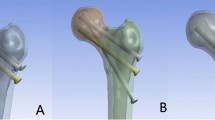

Assembly of internal fixation and the femoral neck fracture model

Grouping situation: FNS group: the FNS internal fixation device was placed in the center of the femoral neck.

FNS-LOW group: the FNS internal fixation device was placed in the low of the femoral neck.

FNS-CS group: the FNS internal fixation device is placed in the low of the femoral neck. Insert the cannulated screw in a limited position between the FNS anti-rotation screw and the cortex above the femoral neck, the distal end of which is less than 5 mm from the cortex of the femoral head.

The assembled model has been imported into Abaqus 6.14 software for automatic mesh division processing. The number of nodes and elements of the finite-element model are shown in Table 2 (Fig. 1c).